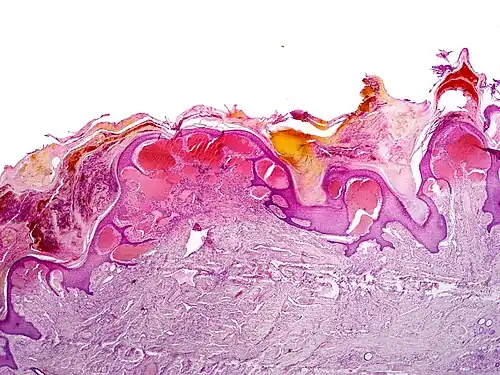

Angiokeratomas characteristically have large dilated blood vessels in the superficial dermis and hyperkeratosis (overlying the dilated vessels).

Scrotal angiokeratoma; visible large dilated blood vessels and hyperkeratosis -

Scrotal angiokeratoma (Mibelli type); blood vessels close to the epidermis